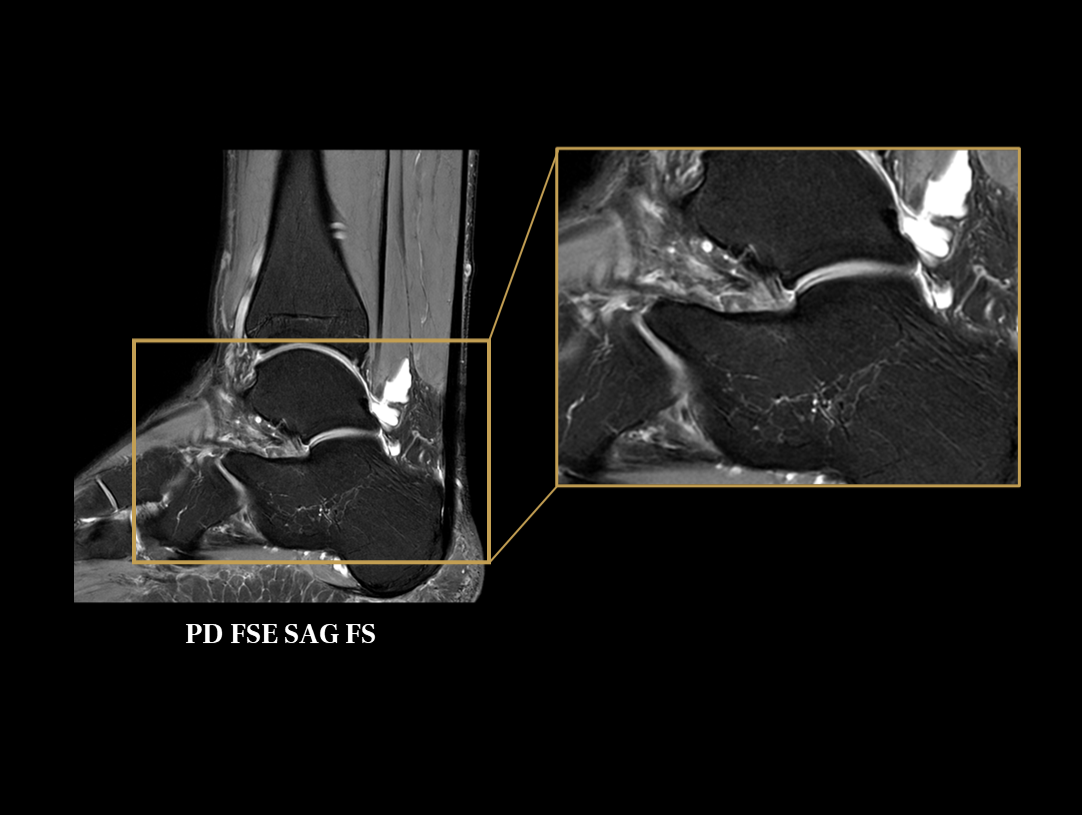

The high performance gradients improve data acquisition and scanning speed, which achieves higher work efficiency.

The 48 high-channel RF complements our integrated high-density coils, resulting insignificant image SNR increase.

The powerful 3.0T magnet uses a 170 cm short-magnet design to ensure high homogeneity of the magnetic field, which provides a solid foundation for fast imaging and excellent fat saturation over a large FOV, as well as outstanding off-center imaging.